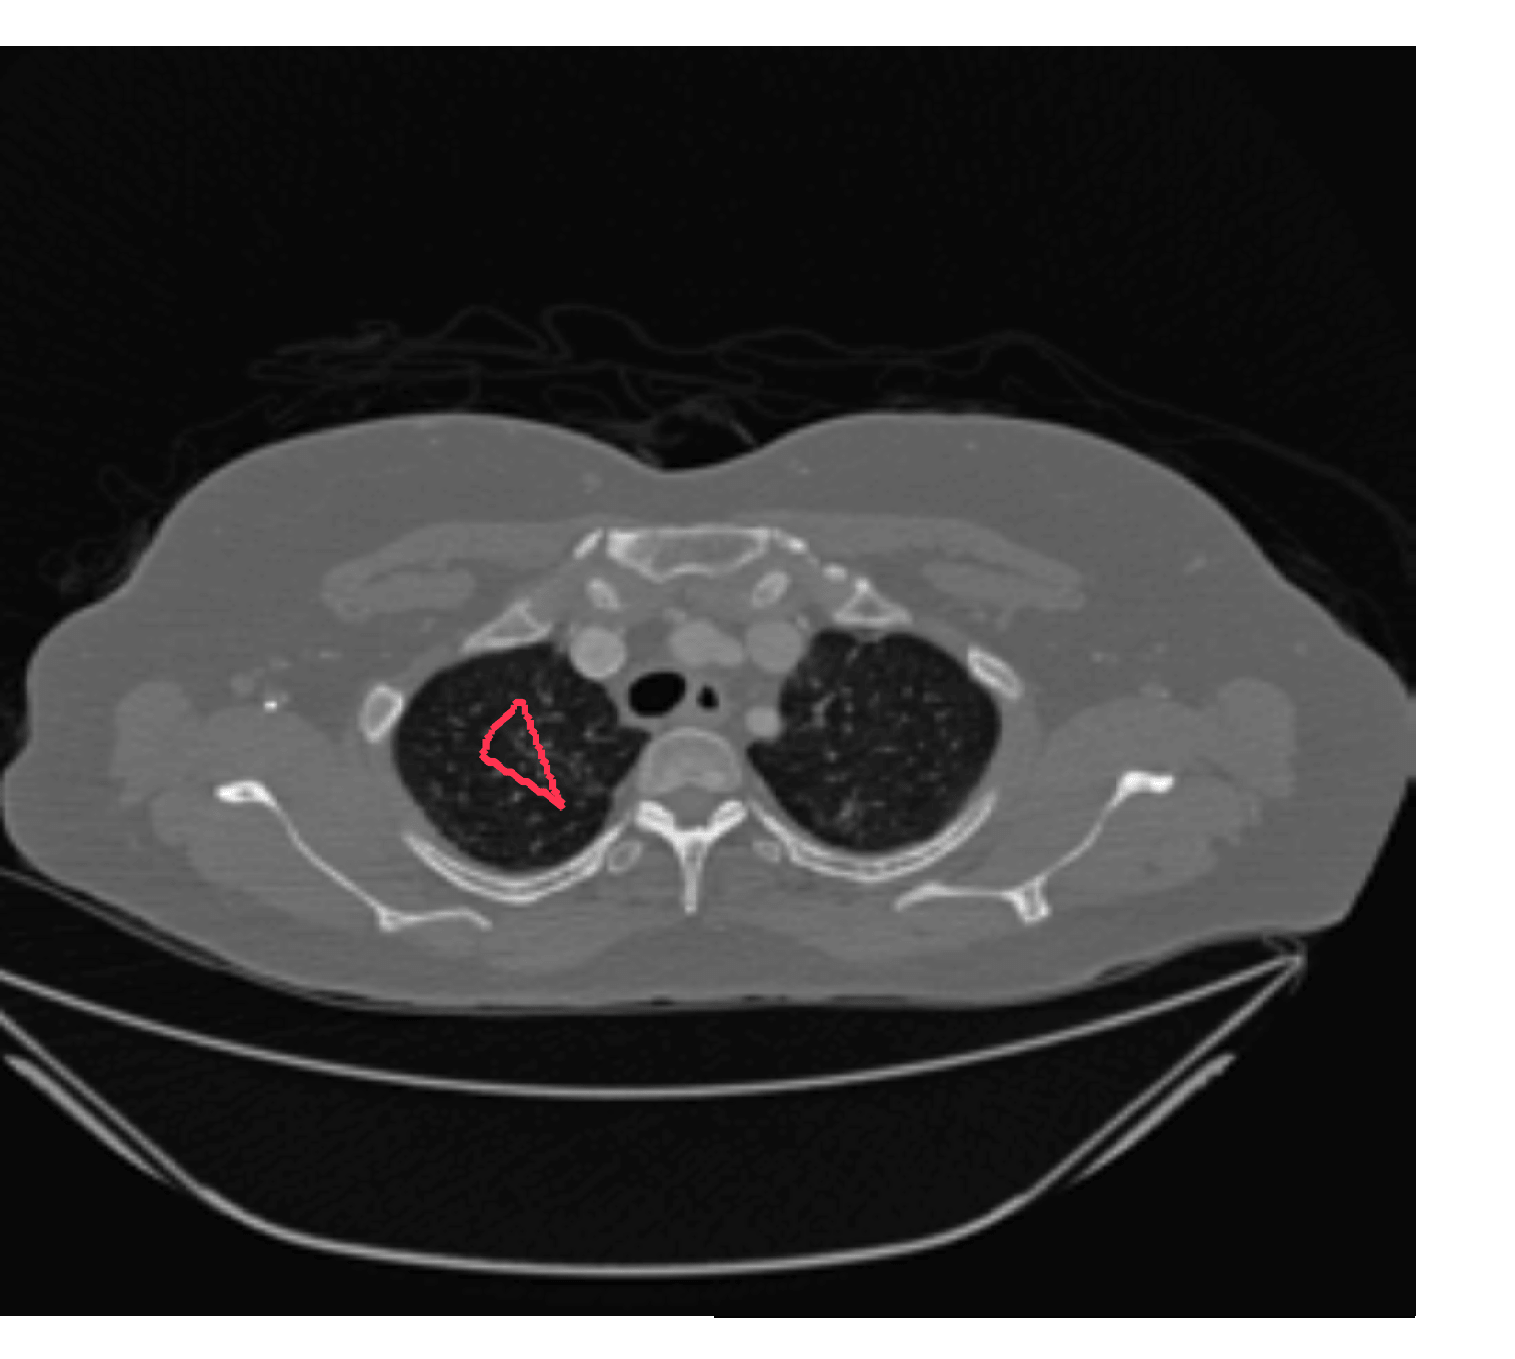

We now introduce two recent methods that incorporate user input to perform selective segmentation. Each involves input in the form of foreground/background regions to indicate relevant structures of interest. An example of this can be seen in Fig. 18, where red regions indicate foreground and blue regions indicate background. We compare against the work of Nguyen et al. Nguyen:12 , which uses a similar convex relaxation framework to the proposed approach, and Dong et al. SRW , which uses a variation of the random walk approach. We summarise the essential aspects of each approach in the following.

Test Images. We will perform initial tests on the images shown in Figs. 5–7. We have provided the ground truth and initialisation used for each image. Test Images 1–3 are synthetic, Test Image 4 is an MRI scan of a knee, Test Images 5–6 are abdominal CT scans, and Test Images 7–9 are lung CT scans. They have been selected to present challenges relevant to the discussion in §2. We focus on medical images as this is the application of most interest to our work. In the following we will discuss the results in terms of synthetic images (1–3) and real images (4–9). We also test the proposed approach on a larger data set of 30 CT images (a sample of which is presented in Fig. 18), comparing against existing selective methods detailed in §3.

In order to further establish the robustness of our method, we now introduce the results of testing our approach against competing interactive segmentation methods on a larger data set. The results are presented in Fig. 17, showing a boxplot of accuracy in terms of TC on a set of 30 CT images (excluding outliers). The target structure we consider is the spleen, as this consists of a relatively homogeneous foreground, appropriate for the approach considered. The data has been manually contoured providing ground truth data for the image set. We compare CAC Nguyen:12 and SRW SRW against our method with five variations of user input for each image. It is worth emphasising here that the input used in the tests is identical for each approach and was not refined in any way. It was designed to mimic what a user, unfamiliar with each approach, might select intuitively. A representative example for three images is shown in Fig. 18. This shows foreground (red) and background (blue) user input regions. For our method, we define the red region as as discussed in §1 and enforce hard constraints on the blue region. We refer to the results of the proposed approach using this input as Ours (i). We also include results of randomising the user input in an identical way to §7.3. For each image we generate 1000 simulated user input choices, which we present as Ours (ii). It is important to note that the difference between Ours (i) and (ii) is only the definition of . The method and parameters are fixed between each.